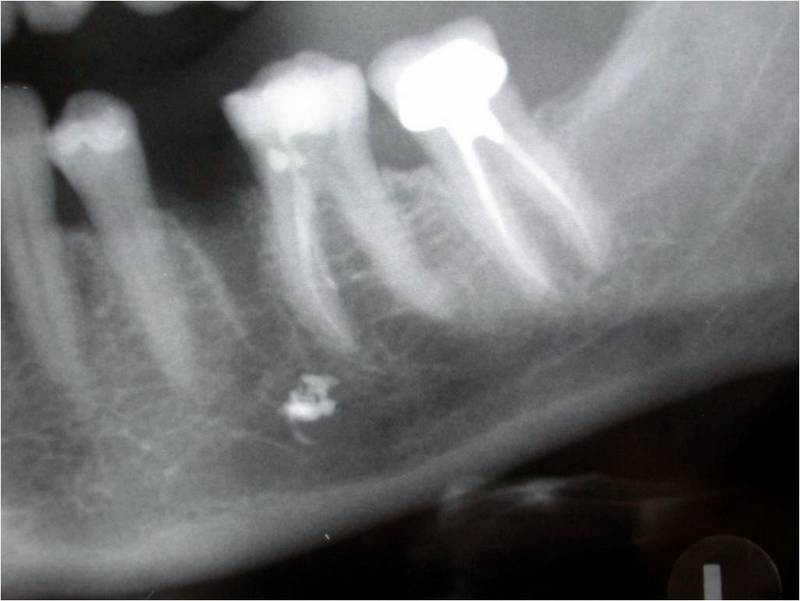

Numb Lip Caused By Root Material